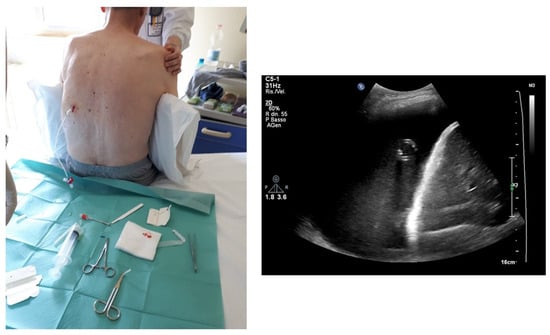

6.1. Position of the Patient

6.2. Choice of the Probe

6.3. How to Set the Sterile Field and Local Disinfection

6.4. The Procedure